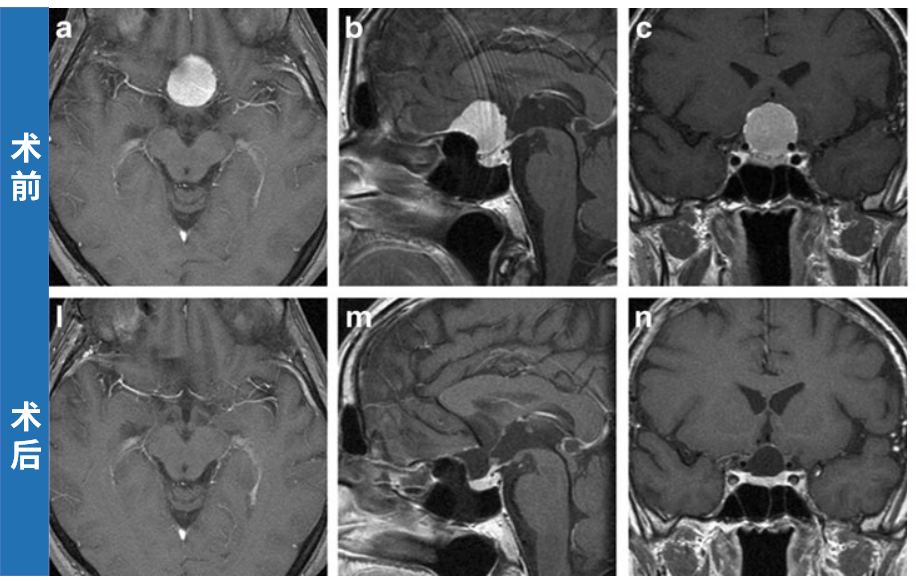

a–c 术前增强T1加权MRI,均显示鞍结节脑膜瘤

l–n 术后39个月增强T1加权MRI,均未见肿瘤残留或复发